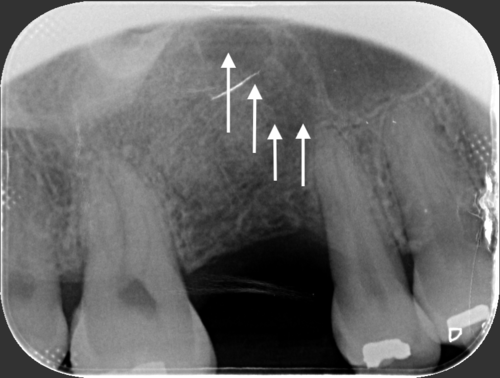

Low dose scan, high value image (Better diagnosis and treatment planning)

Getting your implant as soon as possible (after tooth loss) is the best way to reduce bone loss and avoid bone graft.

Bone loss happens immediately after you lose your teeth

Note: sinus floor will also drops down and further reduce available bone

Low Sinus Floor

Indirect Sinus Lift

Low Sinus Floor

Lateral Sinus Lift

Severe Bone Loss

Chin Block